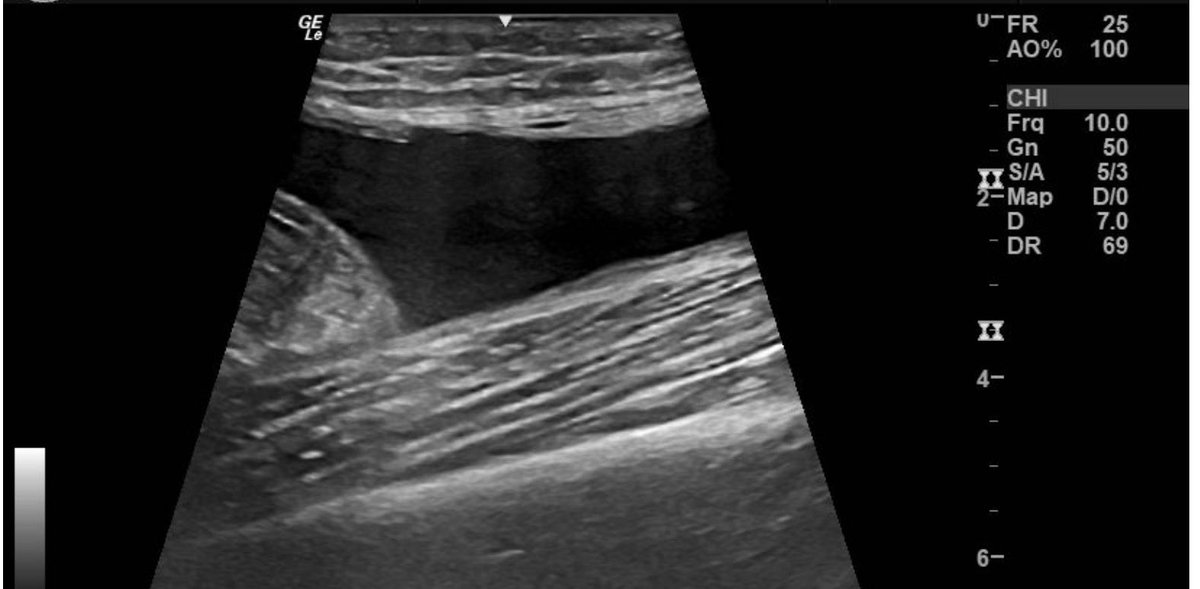

No differences in prevalences of pubic-related radiographic findings between football players with and without groin pain! Great to see another online paper from my PhD🤩 It is open access! 🆓 ⬇️ onlinelibrary.wiley.com/journal/160008… @SORC_C